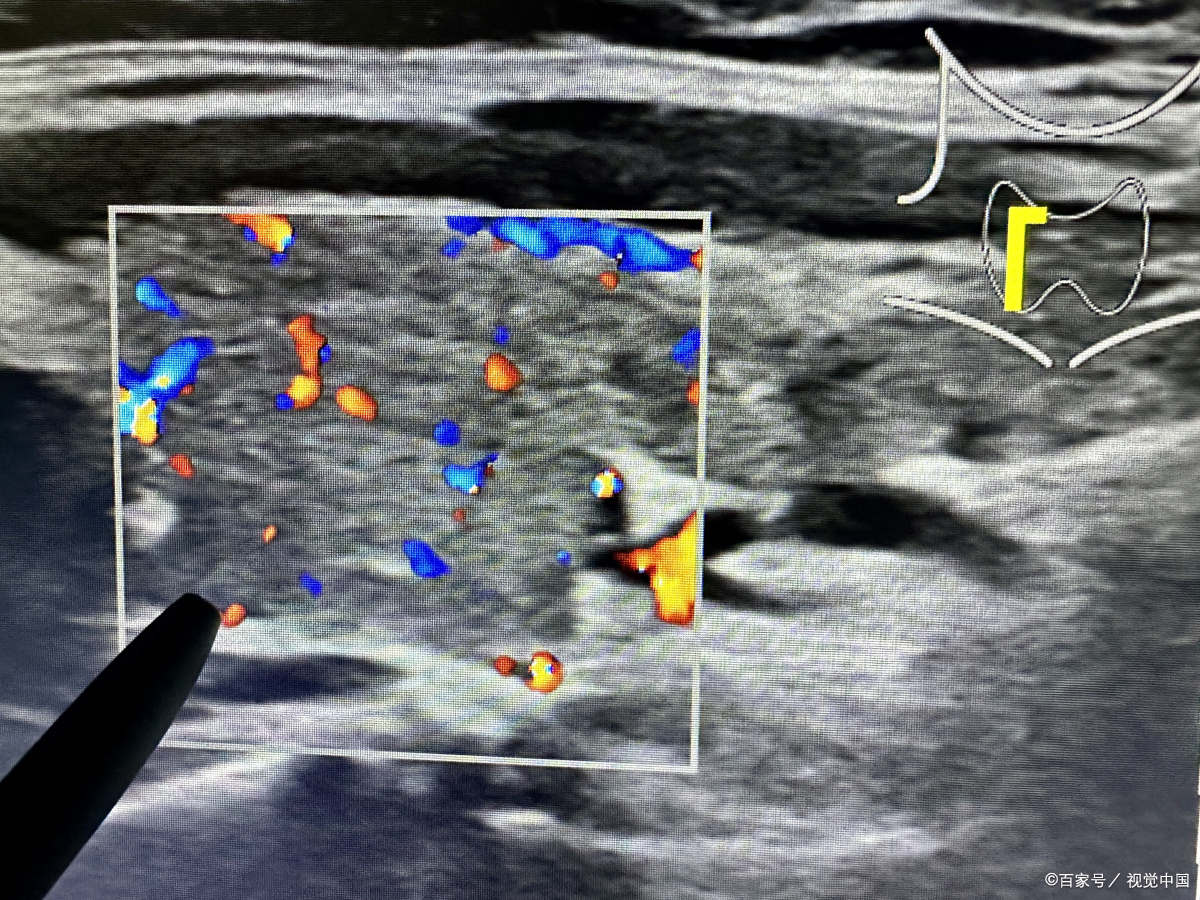

近年来,随着医疗技术的不断发展,治疗甲状腺结节的技术也不断更新迭代,多模态超微介入新一代消融术具有更高的精准度和更小的创伤。它通过多个模态成像技术,可以更全面地获取病变部位的详细信息,包括病变的大小、形状、位置、与周围组织的毗邻关系等。这使得医生能够更准确地判断病变的性质和范围,从而制定更加个性化的治疗方案。

多模态超微介入术:1、灭活彻底 不易复发;2、安全隔离周边器官组织;3、促进病灶加速吸收代谢;4、四维成像清晰度及准确度高,能够多方位、多角度地观察结节。